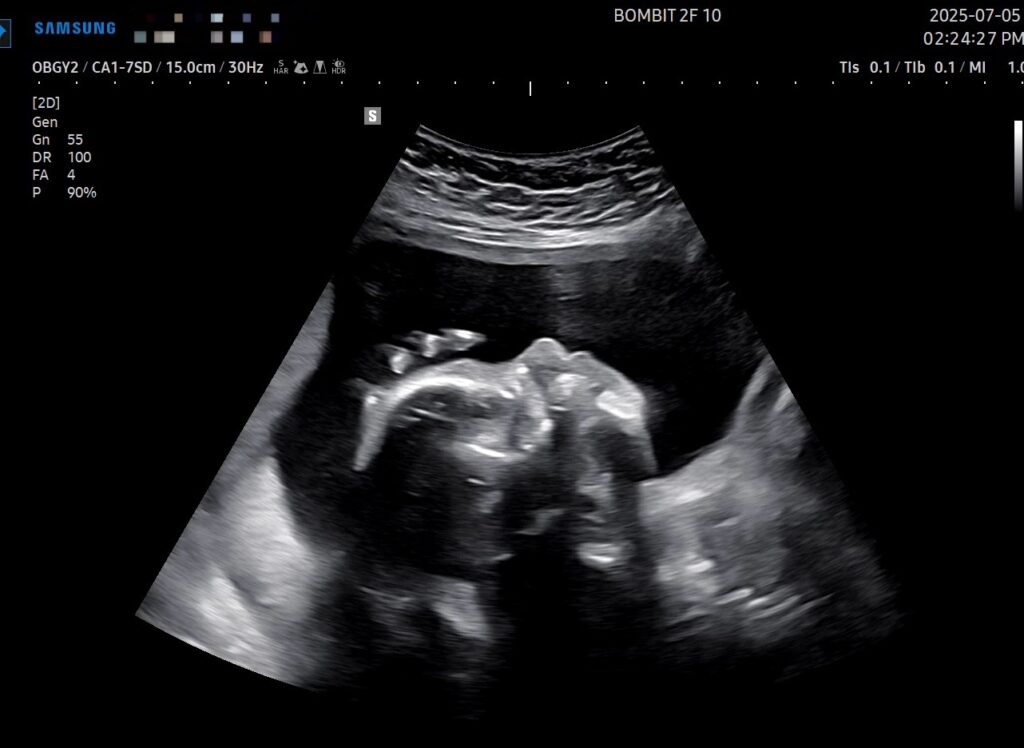

이건 초음파 사진!

This image has an empty alt attribute; its file name is videocapture_20250708-1606305378070047750685714-1024x748.jpg

초기 때는 초음파 옆모습 단면이 아기처럼 예쁘게 보였는데, 전반적인 크기가 커지면서 눈두덩이랑 턱뼈가 초음파로 적나라하게 드러나게 되었다. 그래서 초음파 사진이 약간 괴기스러워졌다..ㅋㅋㅋ